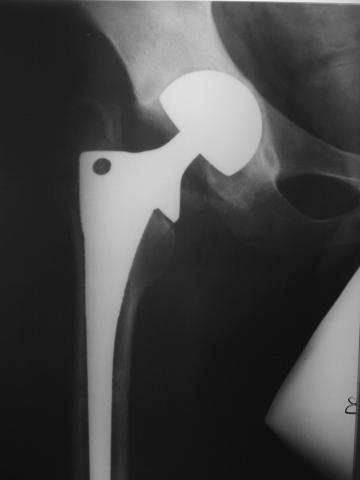

Лечился в стержневом аппарате по месту жительства. АВФ демонтировали через полгода из-за воспаления в области стержней (рис 2). После демонтажа в течение месяца больной лихорадил до 38*, были боли в бедре. Эти явления исчезли после курса антибиотиков. Через год после травмы в ЦРБ ему имплантировали биполярный протез (рис 3). Рана зажила первично. Ходил с костылями, слегка приступая на ногу. На контрольных осмотрах выявлена прогрессирующая протрузия (рис 4-6).

Если нет явных признаков воспаления (клинических и лабораторных) то я бы предпринял одноэтапную ревизию с заменой обоих компонентов сутава. Кольцо

Мюллера не есть антипротрузионное - это моделирующее кольцо и вряд ли здесь подойдет. В данном случае - кольцо Бурша -Шнайдера или Ганса более логичны, так как они истино антипротрузионные. Огромный дефект следует закрыть костью на будущие ревизии. При инфекции - шанс на двухэтапную ревизию есть, но риски значительные. риски выбирает пациент. В любом случае - это следует делать умелыми руками при хорошем материальном обеспечении. А Рыков.

Стоит ли менять сейчас бедренный компонент? Пока явных признаков нестабильности его не видно.

Да, согласен полностью. Burch-Schneider понадежнее будет.